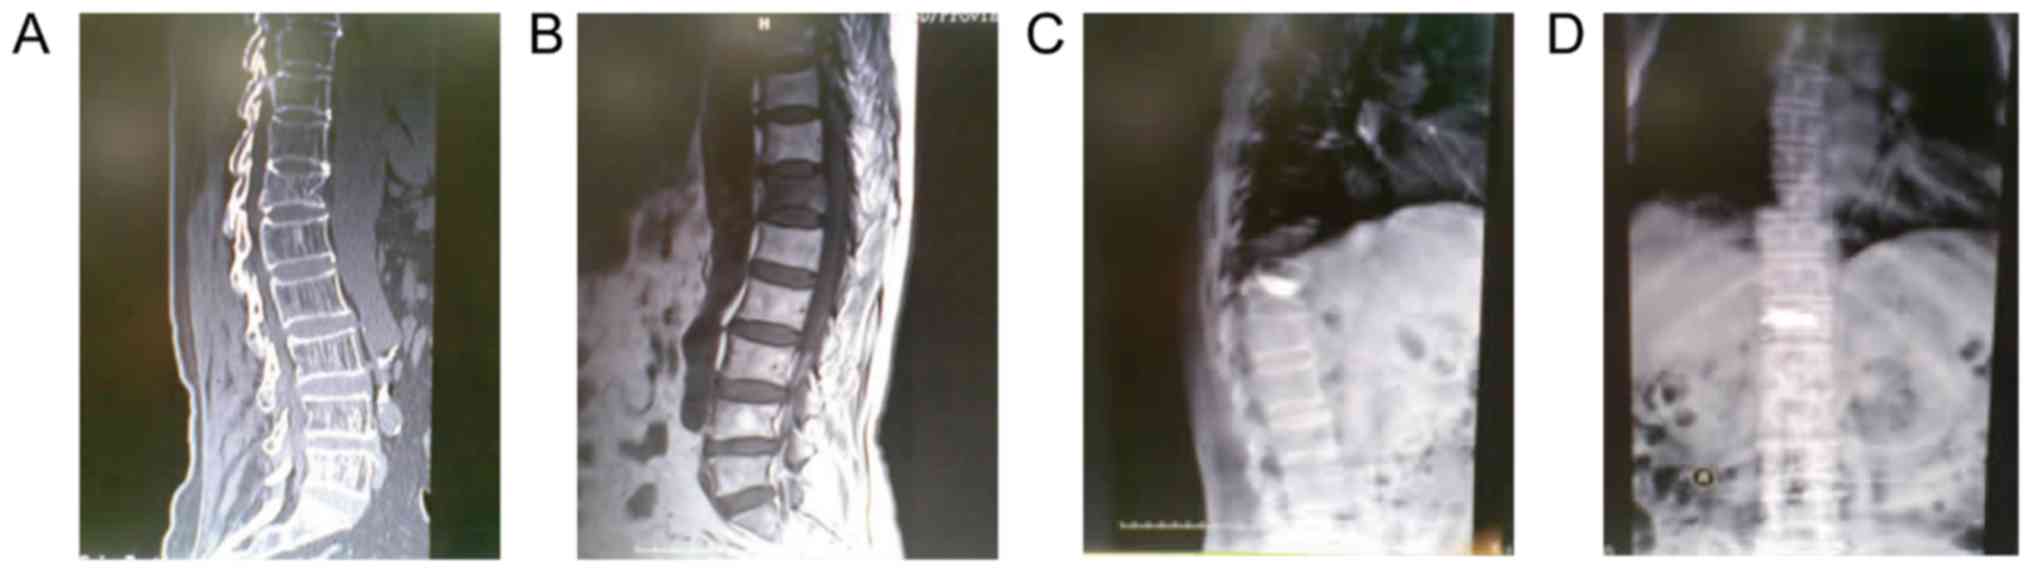

A total of 80 patients with thoracolumbar vertebral fracture who were admitted to were admitted to General Hospital of The Yangtze River Shipping and Wuhan Brain Hospital and The Affiliated Jiangyin Hospital of Southeast University Medical College (Wuxi, China) between January 2014 and March 2016 for combination treatment of percutaneous kyphoplasty and alendronate sodium were enrolled. Before operation, all patients aged below 60 years old were required to undergo computed tomography (CT) and magnetic resonance imaging (MRI) (Fig. 1A and B) for diagnosis to rule out those complicated with tuberculosis of thoracolumbar spine, tumors in thoracolumbar and vertebra, coagulation disorders, dysfunctions in lumbar vertebra, heart, lung, liver or kidney, diseases in spine or nervous system, mental diseases, diseases in consuming system, lateral displacement or rotation in fracture site, complete spinal cord injury after fracture or cauda equina syndrome. In addition, all patients had signed the written informed consent, and the protocols of this study had been approved by the Ethic's Committee of General Hospital of The Yangtze River Shipping and Wuhan Brain Hospital and The Affiliated Jiangyin Hospital of Southeast University Medical College.

Figure 1.

Pre- and post-operative images. (A) Pre-operative CT images. (B) Pre-operative magnetic resonance imaging images. (C and D) Post-operative X-ray images.

Under local anesthesia, all patients underwent percutaneous kyphoplasty, and during the surgery, patients were required to keep in prone with the hip and anterior superior spine being lifted to keep the abdomen suspended for identify the fracture site of vertebra under X-ray. From the pedicle of vertebral arch in the affected vertebra under local anesthesia, locating pin was guided into the 1/3 site of vertebra, and, after the pathway was expanded manually by a drill, reached to the site 1 cm to the anterior edge of vertebra; again, X-ray examination was then performed to guarantee that the tip of pin was in the midline of vertebra. Thereafter, a saccule was inserted with the pressure being adjusted to 160 to 180 psi, and the vertebra was then slowly opened for injection of about 1 ml of bone cement under X-ray, after which the distribution of bone cement should be closely monitored. At 60 sec later, approximately 1 ml of bone cement was again injected, and the distribution range of bone cement should also be closely monitored to avoid the exosmosis of bone cement to the posterior edge veins of vertebra. In this surgery, the amount of bone cement injection was recorded until the bone cement was coagulated, and surgery was completed after patients kept the prone position for 20 min. After surgery, 10 mg alendronate sodium (SFDA approval no. H10980108; CSPC Huasheng Pharmaceutical Co., Ltd., Shijiazhuang, China) was administrated orally in the morning before meal once per day. Additionally, post-operation X-ray of all patients were done to observe the effections of the operation (Fig. 1C and D). All patients underwent 1-year follow-up. Recurrence of fracture and the site were identified through the clinical symptoms and the results of MRI of spine cord.